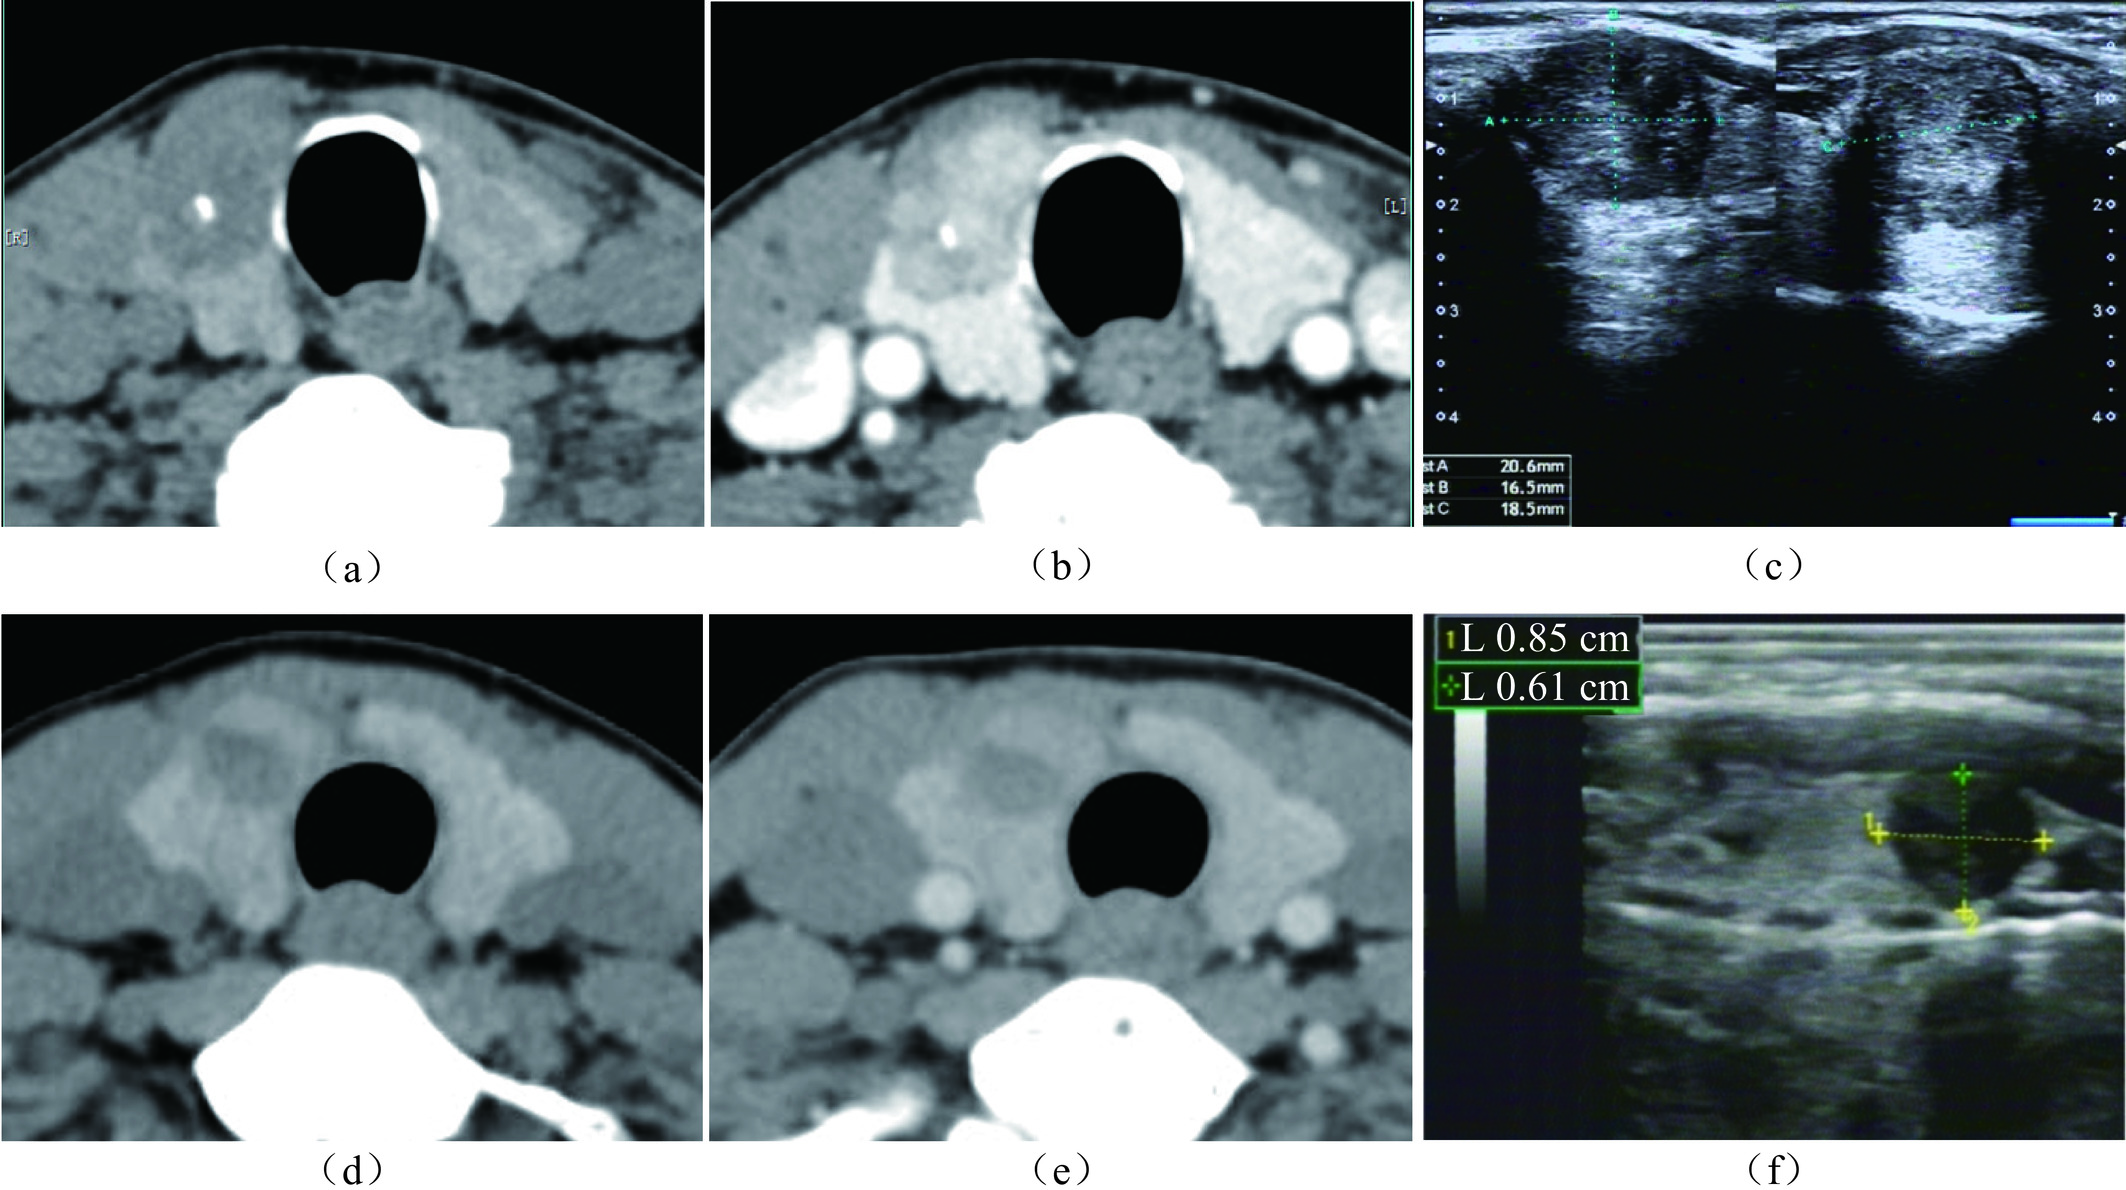

表 4 340例PTC患者7∶3比例随机分组中IRF的比较Table 4. Comparison of IRFs in the training and validation cohorts where 340 PTC patients were randomly divided into at a 7∶3 ratio特征 组别 统计检验 训练组(n=237) 验证组(n=103) T P 年龄分组/例(%) ≤55 141(59.5) 62(60.2) 0.015 0.904 >55 96(40.5) 41(39.8) 性别/例(%) 男 63(26.6) 25(24.3) 0.200 0.655 女 174(73.4) 78(75.7) 边缘/例(%) 规则 68(28.7) 36(35,0) 1.325 0.250 不规则 169(71.3) 67(65.0) 被膜接触/例(%) 0 45(19.0) 14(13.6) 1.903 0.593 < 25% 68(28.7) 28(27.2) 25%~50% 64(27.0) 32(31.1) > 50% 60(25.3) 29(28.2) 最大径/例(%) ≤10 mm 164(69.2) 69(67.0) 0.162 0.687 >10 mm 73(30.8) 34(33.0) ![]() 图 3 Nomogram预测CLNM的性能演示(界值为0.303)注:患者1,男性,44岁,PTC病例,CLNM阳性。CT平扫示右叶中下部类圆形病灶,内见钙化,与甲状腺被膜接触约75%(a),增强后不均匀强化(b),超声显示低回声区,境界清晰,边缘光整,约20.6×16.5×18.5 mm(c),对照Nomogram:男性(38分)+年龄 < 55岁(28分)+被膜接触 > 50%(100分)+最大径 > 10 mm(45分)=211分,对应的CLNM预测概率0.73。患者2,女性,37岁,PTC病例,CLNM阴性。右叶内不规则低密度结节,边缘与被膜无接触(d),增强后轻度强化(e),超声显示境界清晰,边缘不光整的低回声区,最大径约8.5 mm(f),对照Nomogram:年龄 < 55岁(28分)+边缘不规则(48分)=76分,对应的CLNM预测概率0.10。Figure 3. Performance of the nomogram for CLNM (cutoff=0.303)

图 3 Nomogram预测CLNM的性能演示(界值为0.303)注:患者1,男性,44岁,PTC病例,CLNM阳性。CT平扫示右叶中下部类圆形病灶,内见钙化,与甲状腺被膜接触约75%(a),增强后不均匀强化(b),超声显示低回声区,境界清晰,边缘光整,约20.6×16.5×18.5 mm(c),对照Nomogram:男性(38分)+年龄 < 55岁(28分)+被膜接触 > 50%(100分)+最大径 > 10 mm(45分)=211分,对应的CLNM预测概率0.73。患者2,女性,37岁,PTC病例,CLNM阴性。右叶内不规则低密度结节,边缘与被膜无接触(d),增强后轻度强化(e),超声显示境界清晰,边缘不光整的低回声区,最大径约8.5 mm(f),对照Nomogram:年龄 < 55岁(28分)+边缘不规则(48分)=76分,对应的CLNM预测概率0.10。Figure 3. Performance of the nomogram for CLNM (cutoff=0.303)Nomogram的预测准确性和临床实用性用Calibration和DCA评价(图4和图5),Calibration显示预测概率和实际概率在训练组和验证组中一致性程度很高。DCA曲线表明,当个体患者预测概率在0.1到0.85范围内,Nomograms预测CLNM的净收益高于无预测组或全部干预组。

图 3 Nomogram预测CLNM的性能演示(界值为0.303)

注:患者1,男性,44岁,PTC病例,CLNM阳性。CT平扫示右叶中下部类圆形病灶,内见钙化,与甲状腺被膜接触约75%(a),增强后不均匀强化(b),超声显示低回声区,境界清晰,边缘光整,约20.6×16.5×18.5 mm(c),对照Nomogram:男性(38分)+年龄 < 55岁(28分)+被膜接触 > 50%(100分)+最大径 > 10 mm(45分)=211分,对应的CLNM预测概率0.73。患者2,女性,37岁,PTC病例,CLNM阴性。右叶内不规则低密度结节,边缘与被膜无接触(d),增强后轻度强化(e),超声显示境界清晰,边缘不光整的低回声区,最大径约8.5 mm(f),对照Nomogram:年龄 < 55岁(28分)+边缘不规则(48分)=76分,对应的CLNM预测概率0.10。

Figure 3. Performance of the nomogram for CLNM (cutoff=0.303)